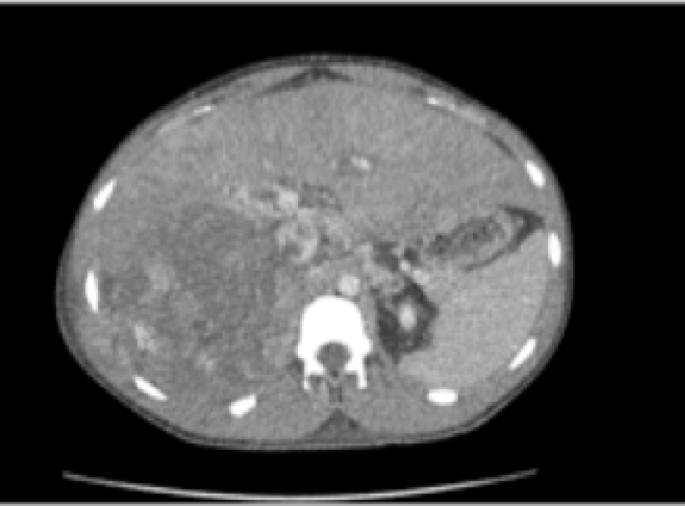

What is the best next step in this child’s management?

The next step in the management of this patient is:

Given the stage, the most appropriate initial treatment of this renal mass would be

The recommended next step for this patient with a presumed cystic renal tumor is